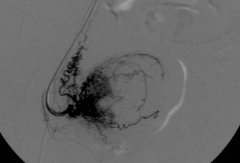

滋养叶细胞肿瘤大出血栓塞

滋养叶细胞肿瘤引起的出血包括致命性大出血和低危险的持续出血...